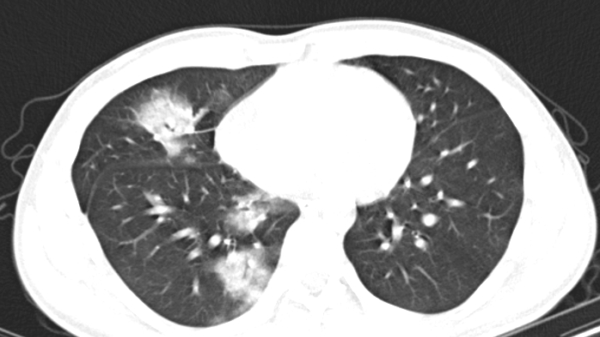

Tại Bệnh viện Đại học Y Dược Buôn Ma Thuột, kết quả chụp CT ngực cho thấy nghi ngờ có dị vật ở thùy phổi phải. Bệnh nhân sau đó được chuyển đến Bệnh viện Đa khoa vùng Tây Nguyên để điều trị.

Theo bác sĩ CKII Đào Anh Dũng, Trưởng khoa Ngoại Tổng hợp, hình ảnh CT và thăm khám lâm sàng cho thấy phổi phải của bệnh nhân có dấu hiệu viêm mạn tính, nhiều khả năng do dị vật gây ra. Ekip tiến hành nội soi phế quản và phát hiện một hạt hồng xiêm nằm ở thùy dưới phổi phải. Dị vật được gắp ra thành công sau gần 2 giờ làm thủ thuật.